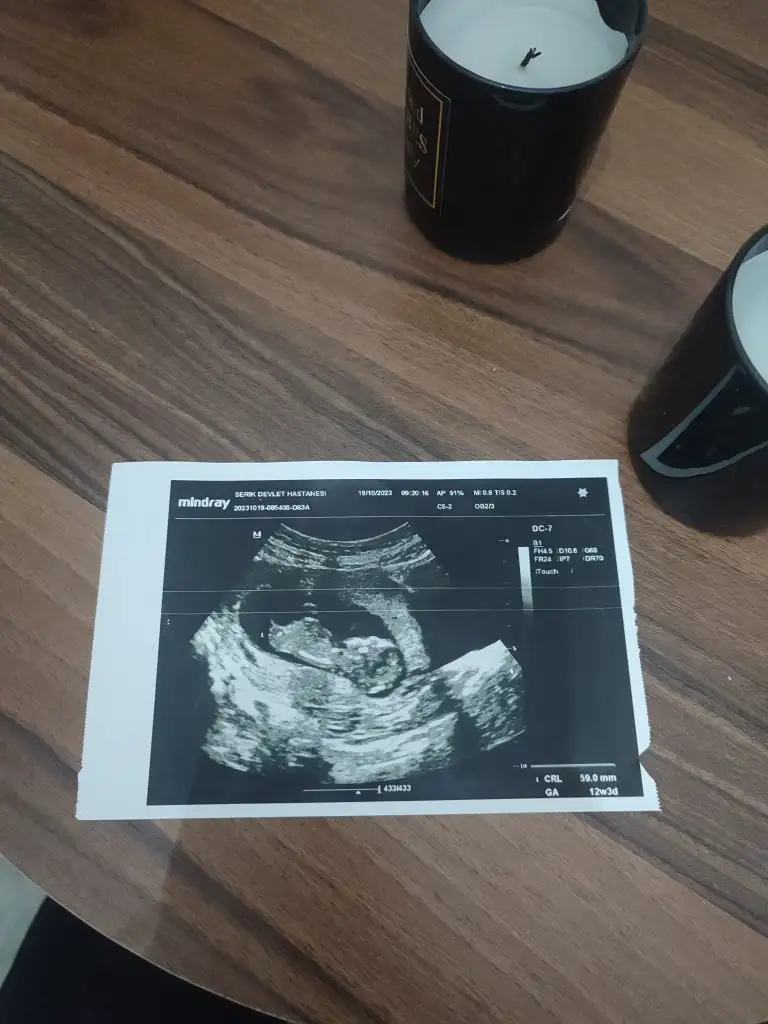

Ya benim içinde tahmin yapar mısınız? İlk resim 12 hafta ikinci ve üçüncü 6 hafta iken son fotoğrafta 14 hafta. Sizce cinsiyeti ne belli oluyor mu?